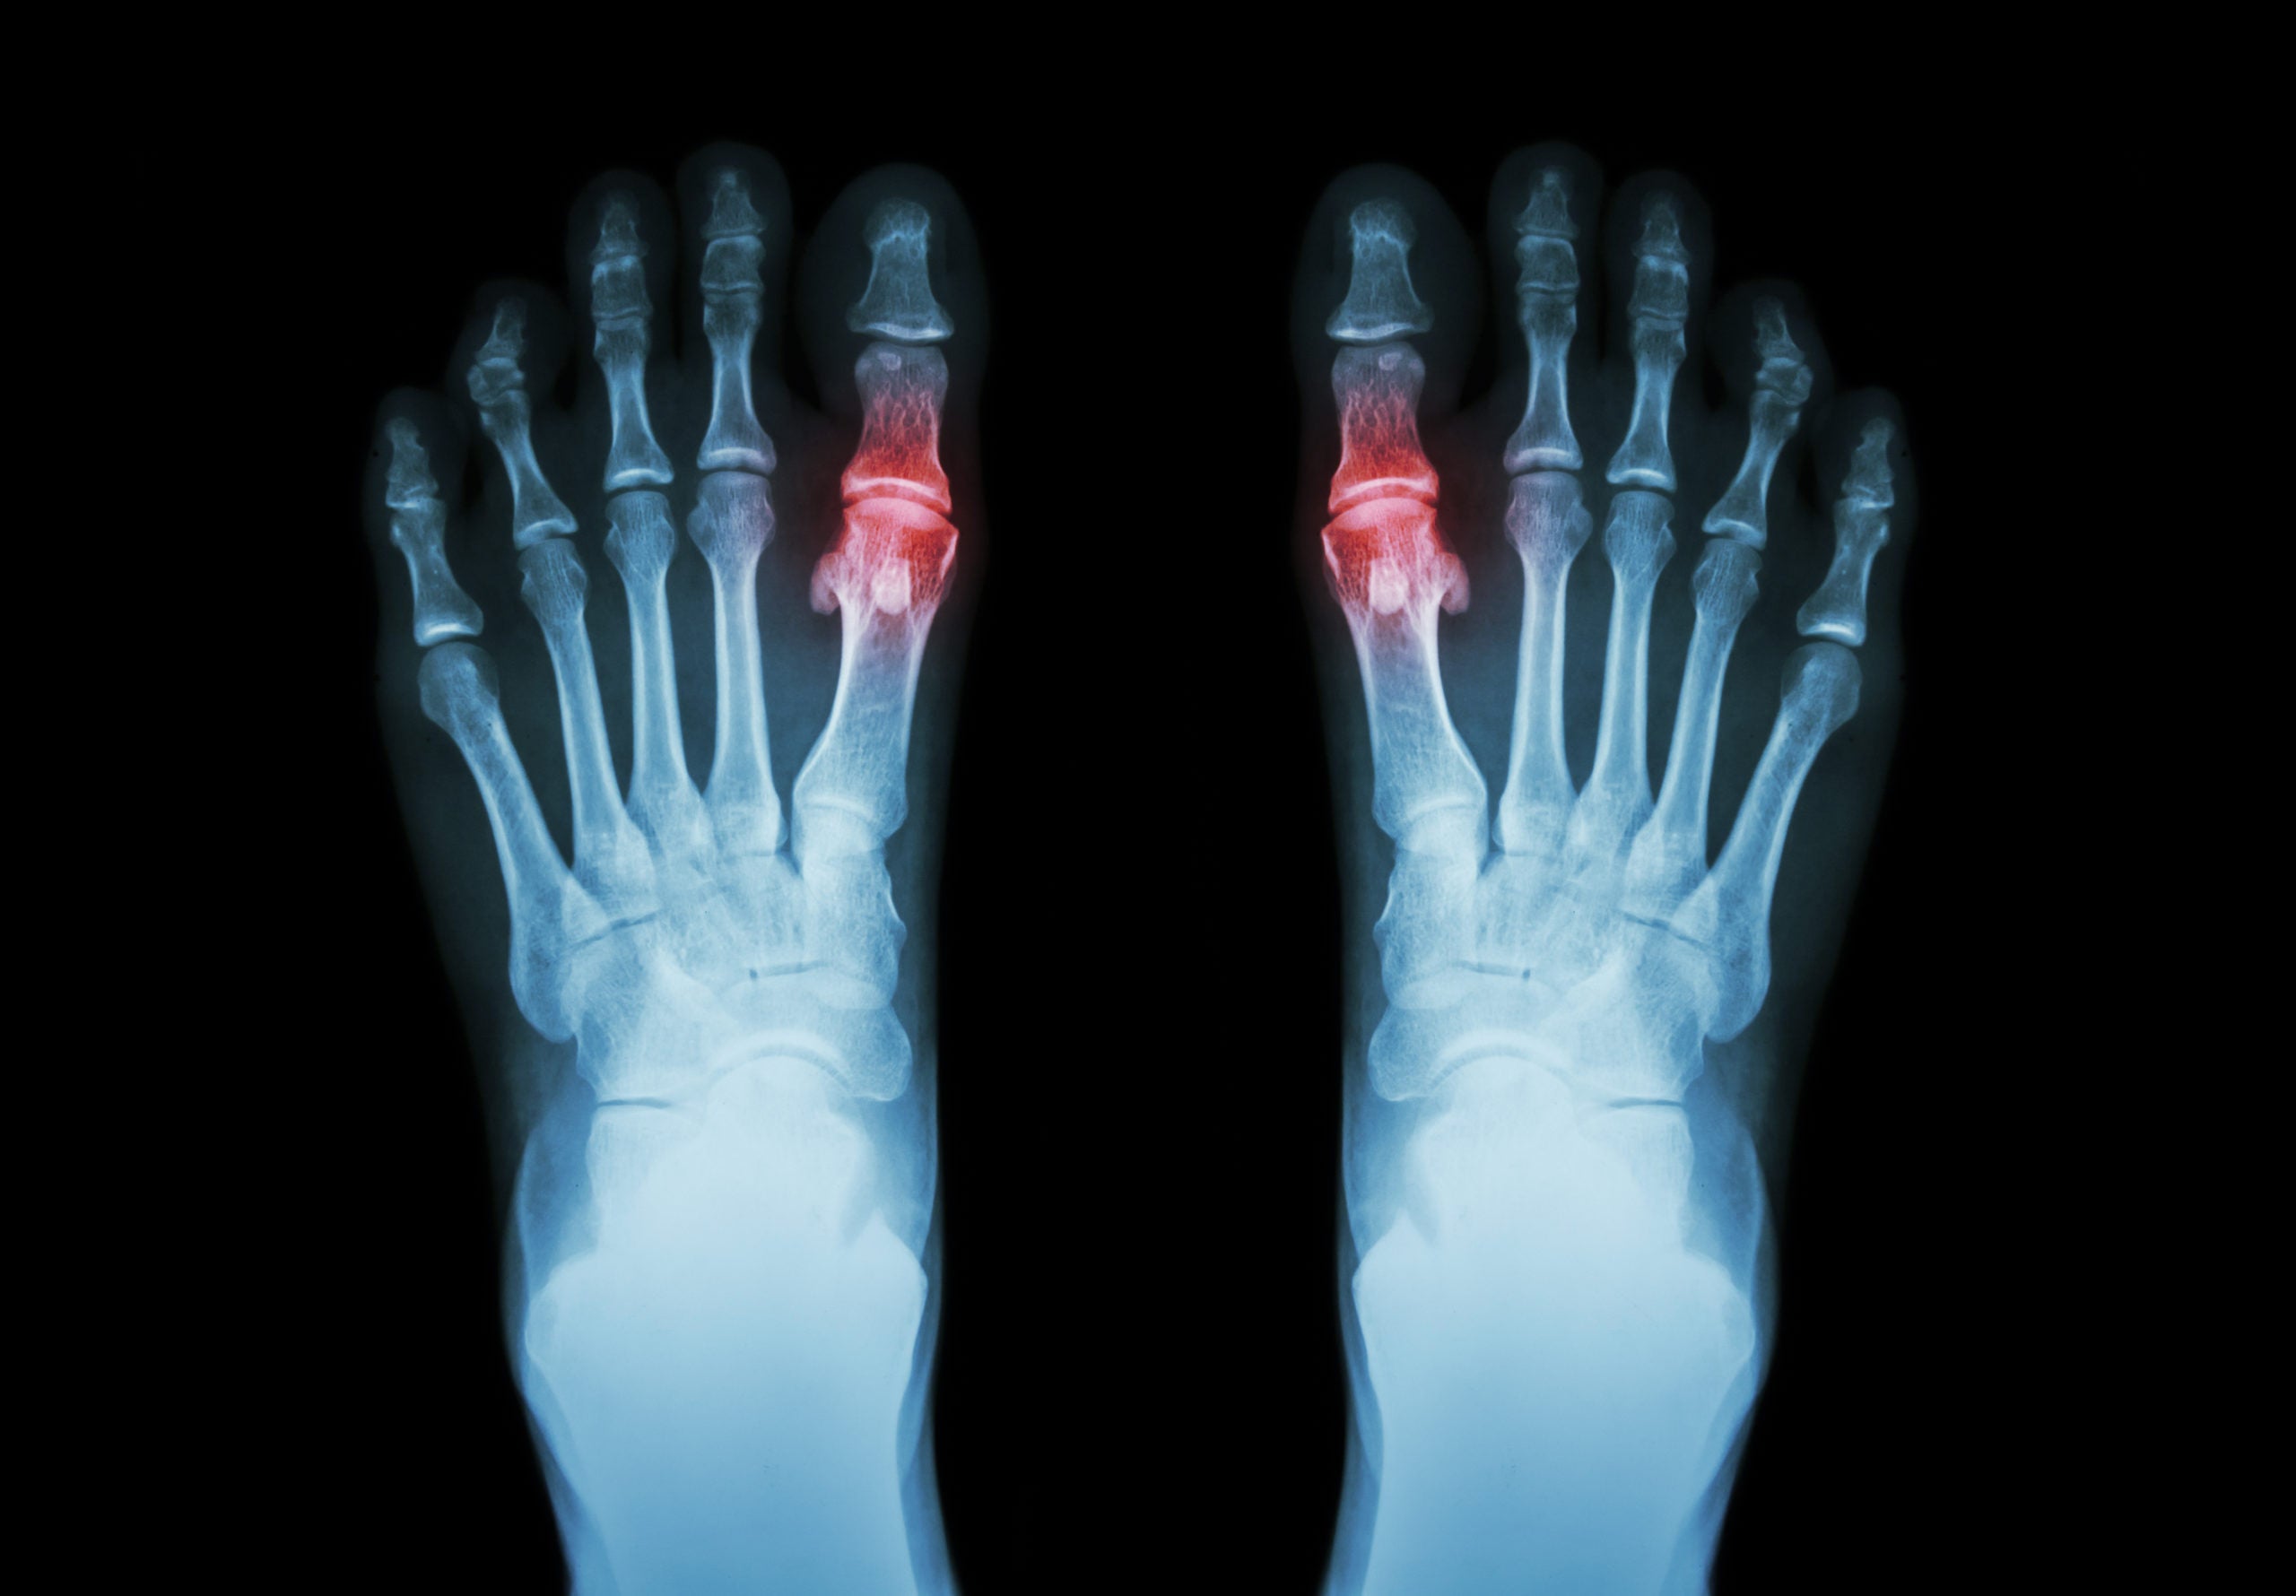

Avoid the Painful Consequences of High Uric Acid

What works… what doesn’t… and what makes it worse When your uric acid levels are high, you may not realize it… but that doesn’t mean it isn’t causi...

How to Reduce Uric Acid and Prevent Future Build-up

Watch as our CEO reveals the all-natural ingredients that you can use to fight the agony of excess uric acid This video reveals Why tart cherry st...